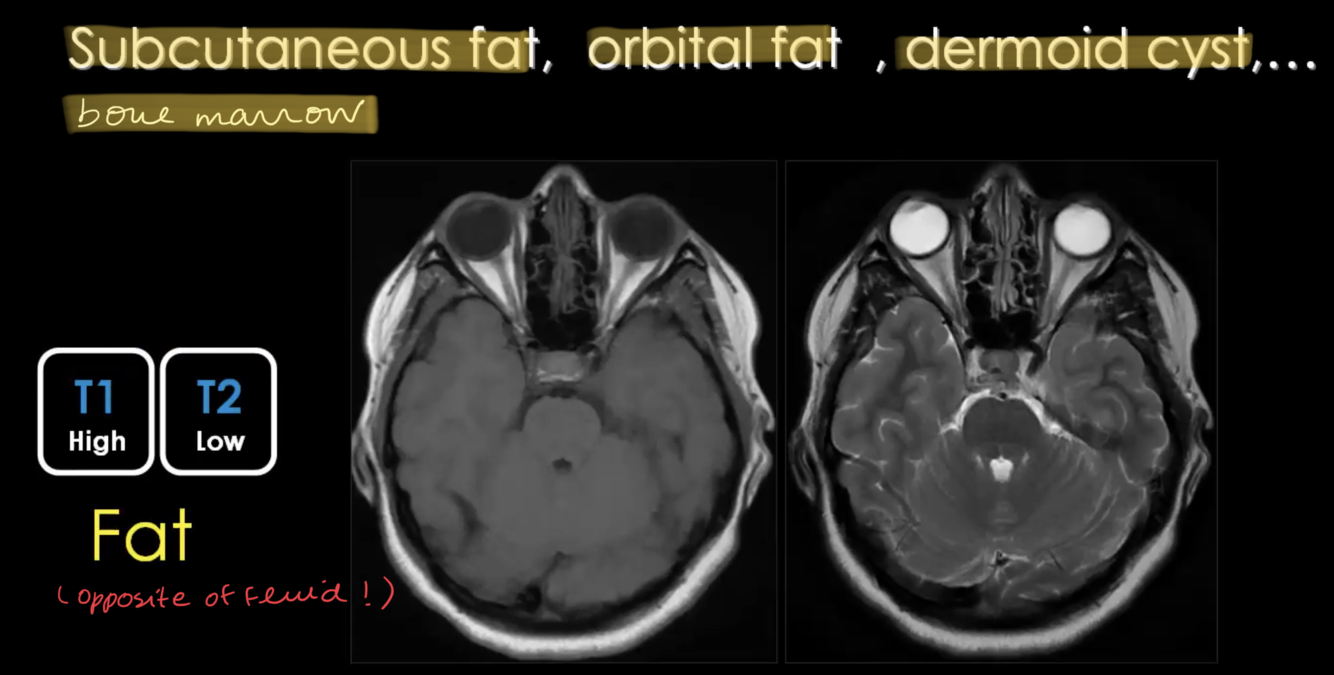

What is HIGH T1 / LOW T2?

Bone Marrow has fat: High T1 / Low T2